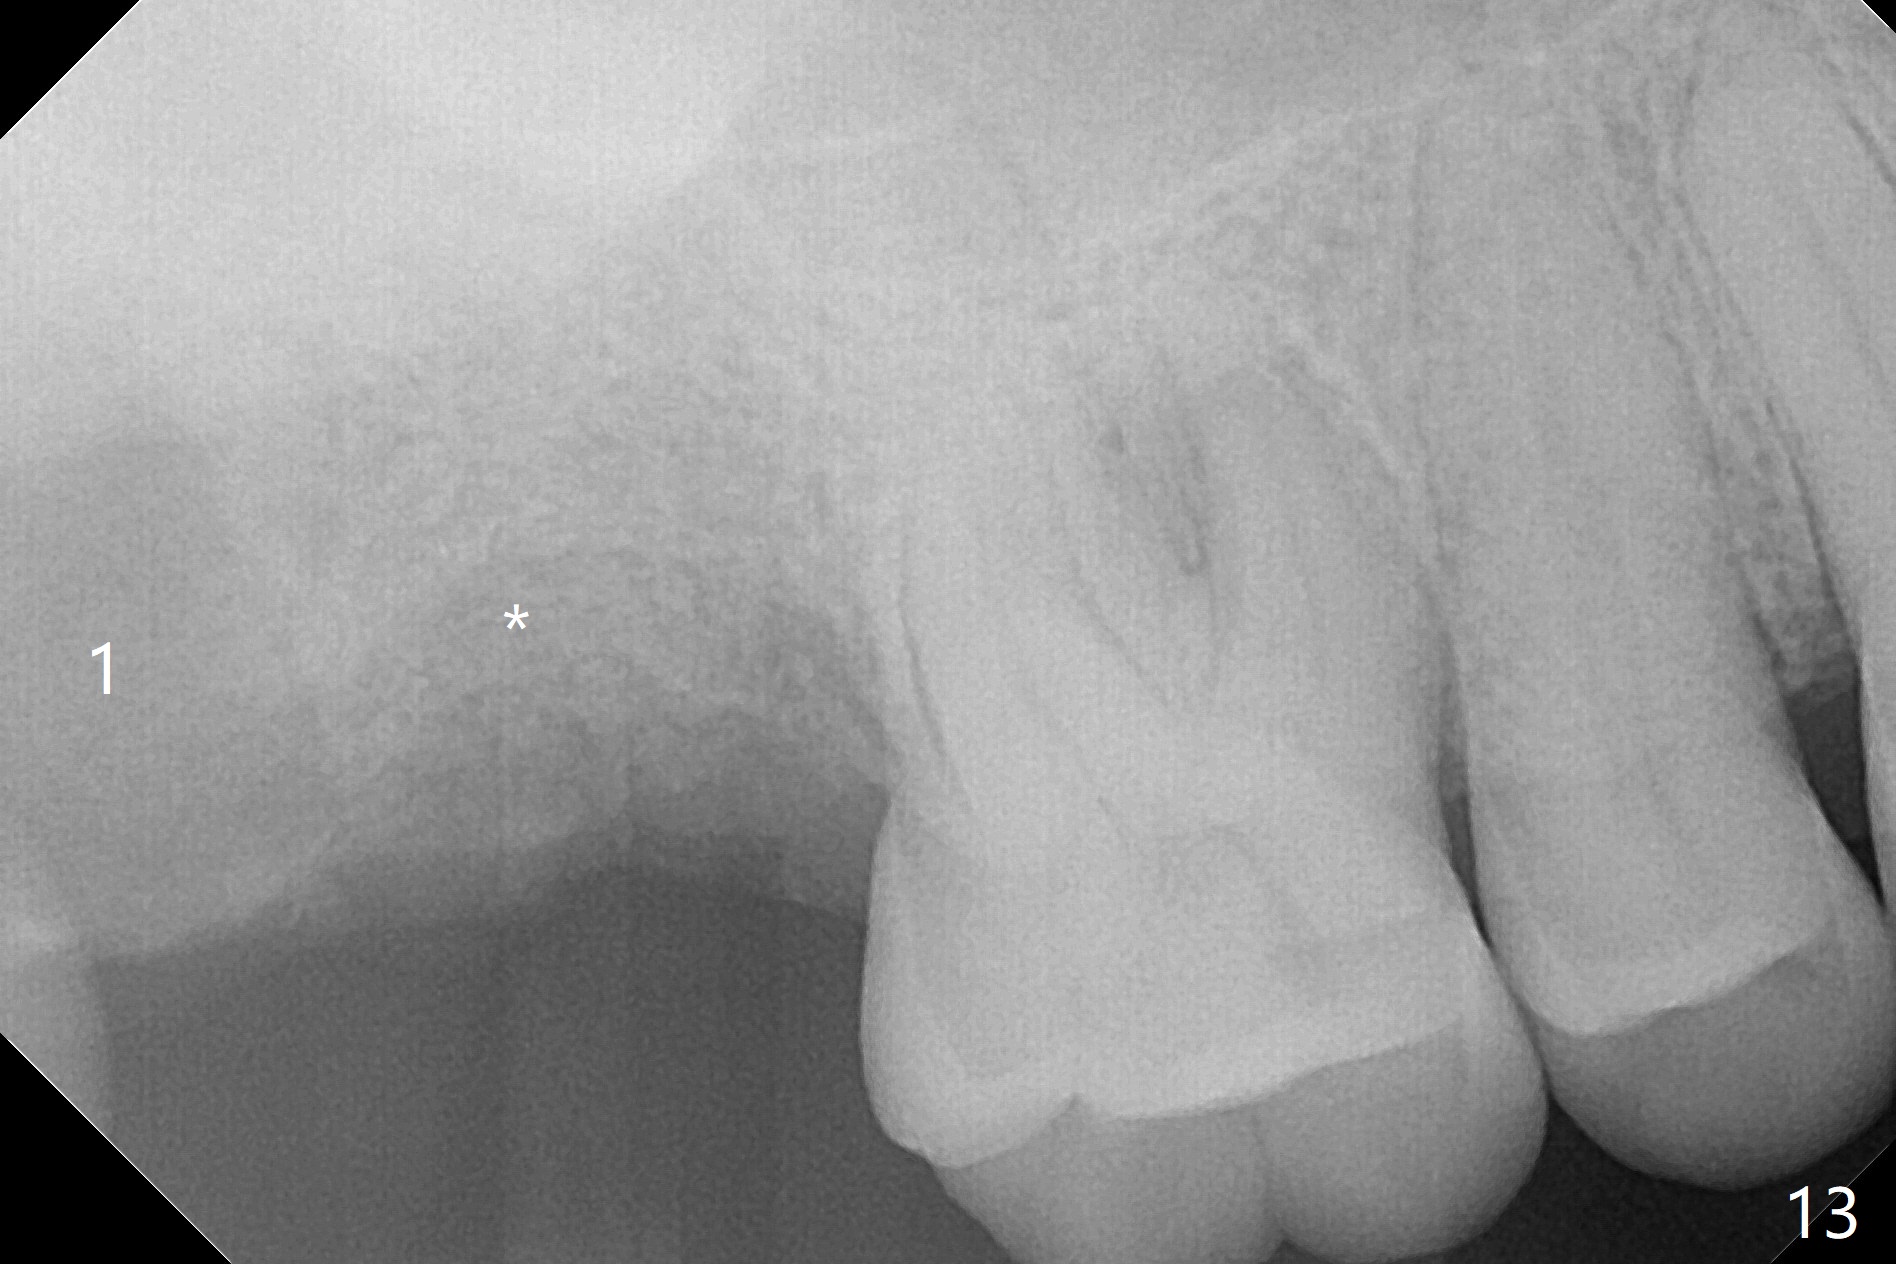

When the 59-year-old man returns for #24 implant placement, the tooth #2 is found to have crack (Fig.1,2 arrowheads), associated with buccal and palatal fistulae (*) and loss of amalgam (Fig.4 *). Abundant granulation tissue is attached to the roots of the affected tooth (Fig.3), indicating severe bone loss. There is a plateau associated with the septum and buccal sockets, which is the site of osteotomy. Magic split and 3 and 3.8 mm Magic Expanders are used to initiate osteotomy. After use of 4.3 mm Magic Drill for about 3 mm, Osteogen plug and allograft are used for sinus lift, followed by insertion of a 4.5x11 mm dummy implant (Fig.5). When a 5.5x9 mm dummy implant is placed with stability, it appears to be seated cervical (Fig.6,7). When a 6x9 mm IBS implant (definitive) is placed with a 6.5x5.5(4) mm abutment, they are seated too deep for provisional (Fig.8). The implant/abutment are removed and replaced by a 6.5x11 mm one in a shallower position; after trimming the same abutment as mentioned above (Fig.9), an immediate provisional is fabricated to keep bone graft in place. Fabrication of Tap with soft tissue markers will reduce the chance of miscalculation and waste of implants. The coronal threads of the implant are covered with bone 6 months postop (Fig.10). One month later when a permanent crown tries in, the implant is found to be loose and tender. A healing abutment is placed. Six months later, the patient returns for crown retry-in. The tooth #1 seems to have shifted mesially (Fig.11 arrow). When the abutment is placed, the implant remains tender and loose. After implant removal with a wrench, there is no granulation tissue or bony defect, including the intact sinus floor (Fig.12 <). Since the tooth #1 has deep periodontal pockets and mobility, the tooth is extracted with abundant granulation tissue. After debridement, Osteogen plug is placed in the socket of #1, while Vanilla graft is placed at the site of #2 (Fig.13 *). Three weeks later, the socket of #2 heals with exposure of Osteogen plug (Fig.14 (B: buccal)).